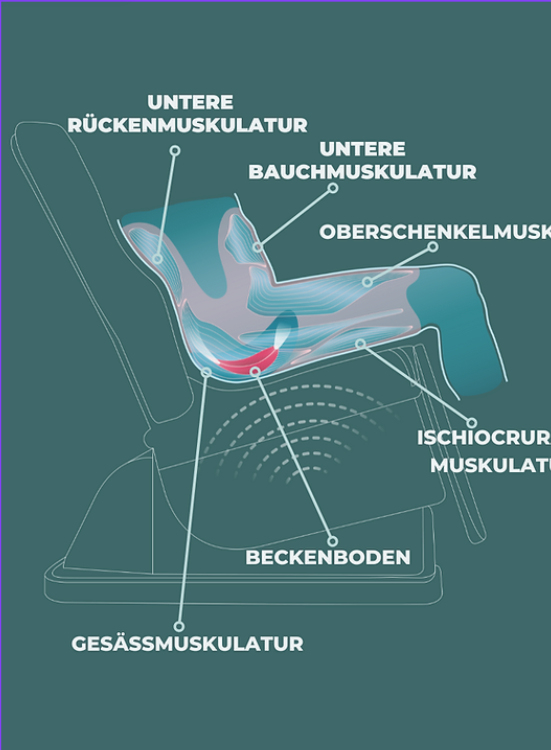

Mit Hilfe nicht-invasiver, modernster Magnetfeldtechnologie können Sie ganz unkompliziert in Alltagskleidung trainieren. Diese Methode ist ideal zur Intensivierung des Eigentrainings sowie eine gute Möglichkeit, motiviert zu bleiben.

Die dem PelviPower™ Magnetfeldtrainer zugrundeliegende Technologie, ist die sogenannte Repetitive Periphere Muskelstimulation (RPMS).

Eine in der Sitzfläche des Stuhls eingebettetes Stimulationssystem, gebildet aus den Magnetspulen und der zugehörigen Elektronik, erzeugt ein Wirkfeld aus repetitiven und kurzen Magnetfeldimpulsen von 200 bis 500 µsek. Dauer und einer magnetischen Flussdichte von bis ca. 2 Tesla.

Die Eindringtiefe beträgt je nach gewählter Intensität 5 bis ca. 15 cm. Der Wirkfelddurchmesser beträgt bis zu 40 cm.

Diese Kontraktionen werden deutlich wahrgenommen und bewirken neben einem effizienten Training, eine verbesserte Durchblutung der Beckenorgane und eine bessere Wahrnehmung und Sensibilität des Beckenbodens und der eigenen Mitte.

Mittels modernster Magnetfeldtechnologie aktiviert, stimuliert und kräftigt der PelviPower-Stuhl die Strukturen des Beckenbodens. Um eine Stärkung bis in die tiefsten Muskelschichten zu erzielen, lösen die Magnetfeldimpulse bis zu 25000 Kontraktionen aus und trainieren so gezielt Ihren Beckenboden. Die Eindringtiefe beträgt je nach gewählter Intensität 5 bis ca. 15 cm. Der Wirkfelddurchmesser beträgt bis zu 40 cm.